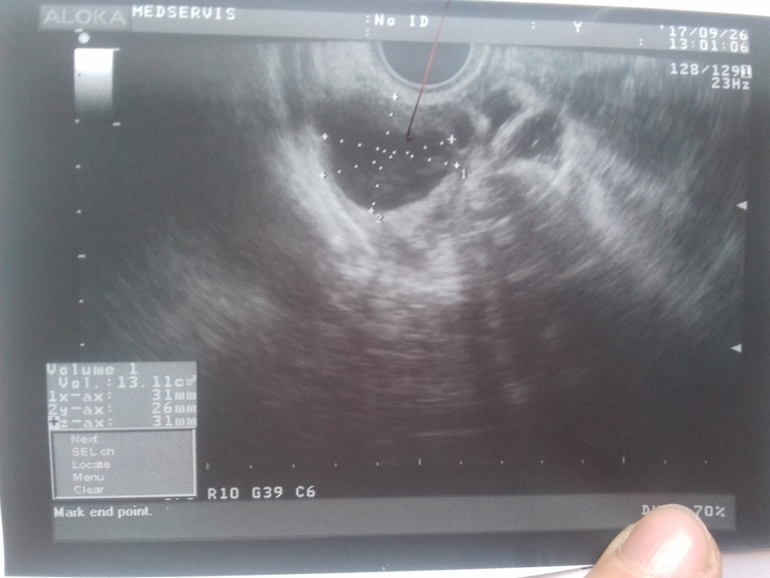

Как отличить кисту ЖТ от фолликулярной?

Какая это киста?

Вам уже верно написали, что определить можно по наличию/отсутствию кровотока. Но к сожалению, не все узисты это смотрят... И пишут потом прост киста, не уточняя какая. По фото можно предположить только, да и то сомнительно. Обычно фолликулярная киста прям темная, почти черная, киста жт - серая с неровными краями. Но это субъективно все.

Есть ещё один способ поверить киста жт или нет - сдать прогик. Если будет в пределах нормы лютеиновой фазы - значит жт.

На фото явно киста желтого тела, она имеет характерное строение, структуры ( ячеистая), фолликулярная киста такой не бывает.

Мне врач несколько раз показывала кисту жт, она всегда как будто сеточкой была, но по фото это нельзя определить, нужно ещё жидкость смотреть и кровоток